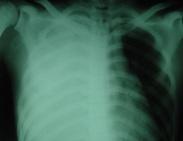

血胸治療

• 血胸

628健康網為您分享有關血胸的癥狀,血胸的治療方法,血胸的預防知識,血胸的癥狀圖片,血胸吃什么藥,血胸怎么治療,血胸患者食...